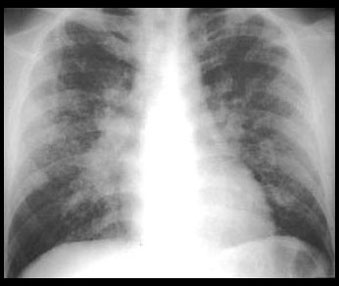

STAGE I STAGE II

Hilar and mediastinal lymphadenopathy. Abnormal lung parenchyma. ( 30% )